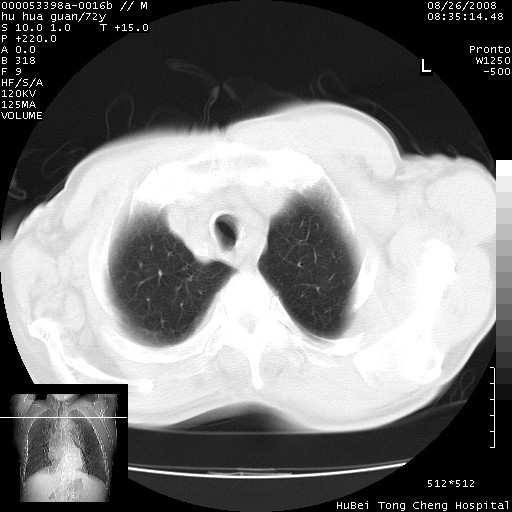

1、右上肺结节病变,肺泡癌不除外,请随诊;左下肺近后纵隔病变,考虑纵隔型肺癌侵犯大血管可能;

2、右下肺背段少许炎症,双侧胸腔积液,右下肺纤维索条。

可以明确的说。肯定不是主动脉夹层破裂出血!考虑为淋巴瘤或间叶组织来源的恶性肿瘤可能性大。右肺小结节建议薄层观察,如能发现恶性征象,那椎前改变就考虑为转移所致。至于双侧少量胸水乃静脉血回流受阻所致。

图像及窗宽窗位均不理想。周围性肺癌/胸腔积液/纵隔积液。

建议排除结核引起的冷脓肿。